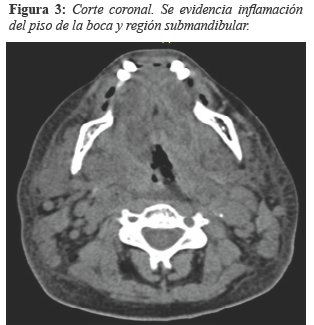

Se indica tomografía computarizada en la que se evidencia cambios de aspecto inflamatorio del piso de la boca y la región submandibular con extensión a las glándulas submandibulares y adenomegalias bilaterales de aspecto reactivo con disminución leve del lumen de la vía aérea a nivel cervical, confirmando el diagnóstico (ver Figura 3 y 4).

Fuente Propia